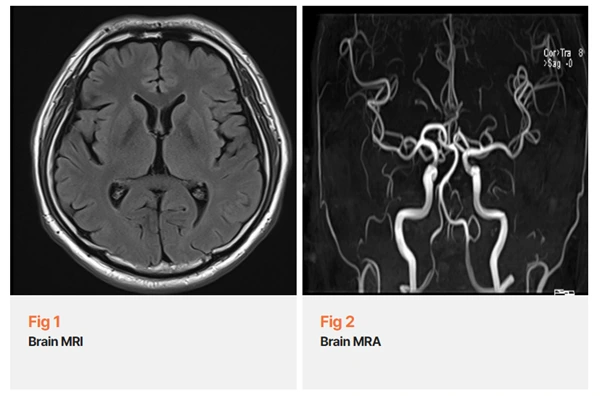

당일 뇌 MRI와 MRA 검사를 시행했고, 다행히 뇌병변이나 뇌혈관 이상은 없었습니다.

그 결과를 설명드릴 때 환자분이 눈에 띄게 안도하시는 모습을 봤어요.

이런 경우를 위해 저희는 뇌 MRI와 MRA 검사를 통해 기질적 원인부터 정확히 배제하는 과정을 거쳐요.